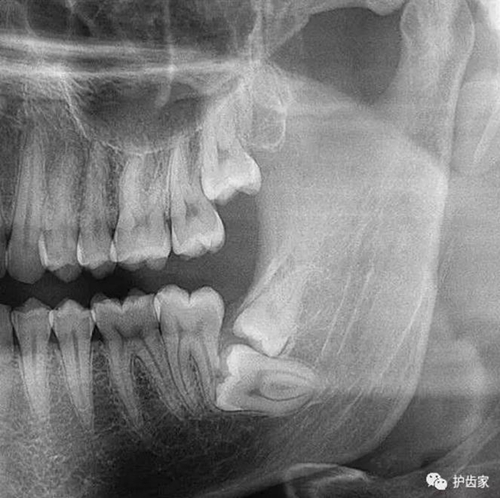

根神經(jīng)線位置千變?nèi)f化,有些離智齒牙根很遠(yuǎn),有些很近,有些甚至穿過智齒根部。

拍片也為了了解下頜神經(jīng)與智齒的關(guān)系,一般離得近,有醫(yī)療風(fēng)險(xiǎn)的,基本沒有醫(yī)生愿意拔,現(xiàn)在沒人為了幾百元,賠上自己的職業(yè)生涯。誰都怕拔智齒,敲打智齒,一不小心,碰到神經(jīng),就攤上大事了。有理都說不清。

通過拍片可以了解牙齒本身:生長方向,牙根數(shù)目,牙根是否彎曲,膨大等。

與重要解剖結(jié)構(gòu)的位置關(guān)系:如上頜磨牙與上頜竇的關(guān)系;下頜磨牙與下頜神經(jīng)管的關(guān)系;兒童在混合牙列期恒牙與乳牙胚的關(guān)系等。可以減少拔牙的風(fēng)險(xiǎn)。